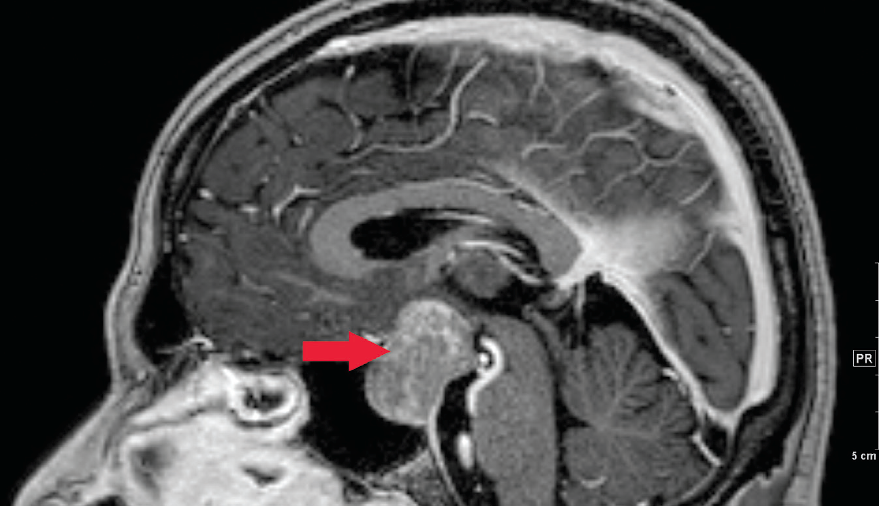

Hypothalamic Hamartoma Radiology Reference Article Radiopaedia Org